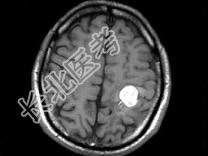

- 单项选择题男,49岁, 右侧肢体无力10余天,伴头昏行走不稳, 根据所提供图像,最可能的诊断是 ( )

E、颅内多发海绵状血管瘤